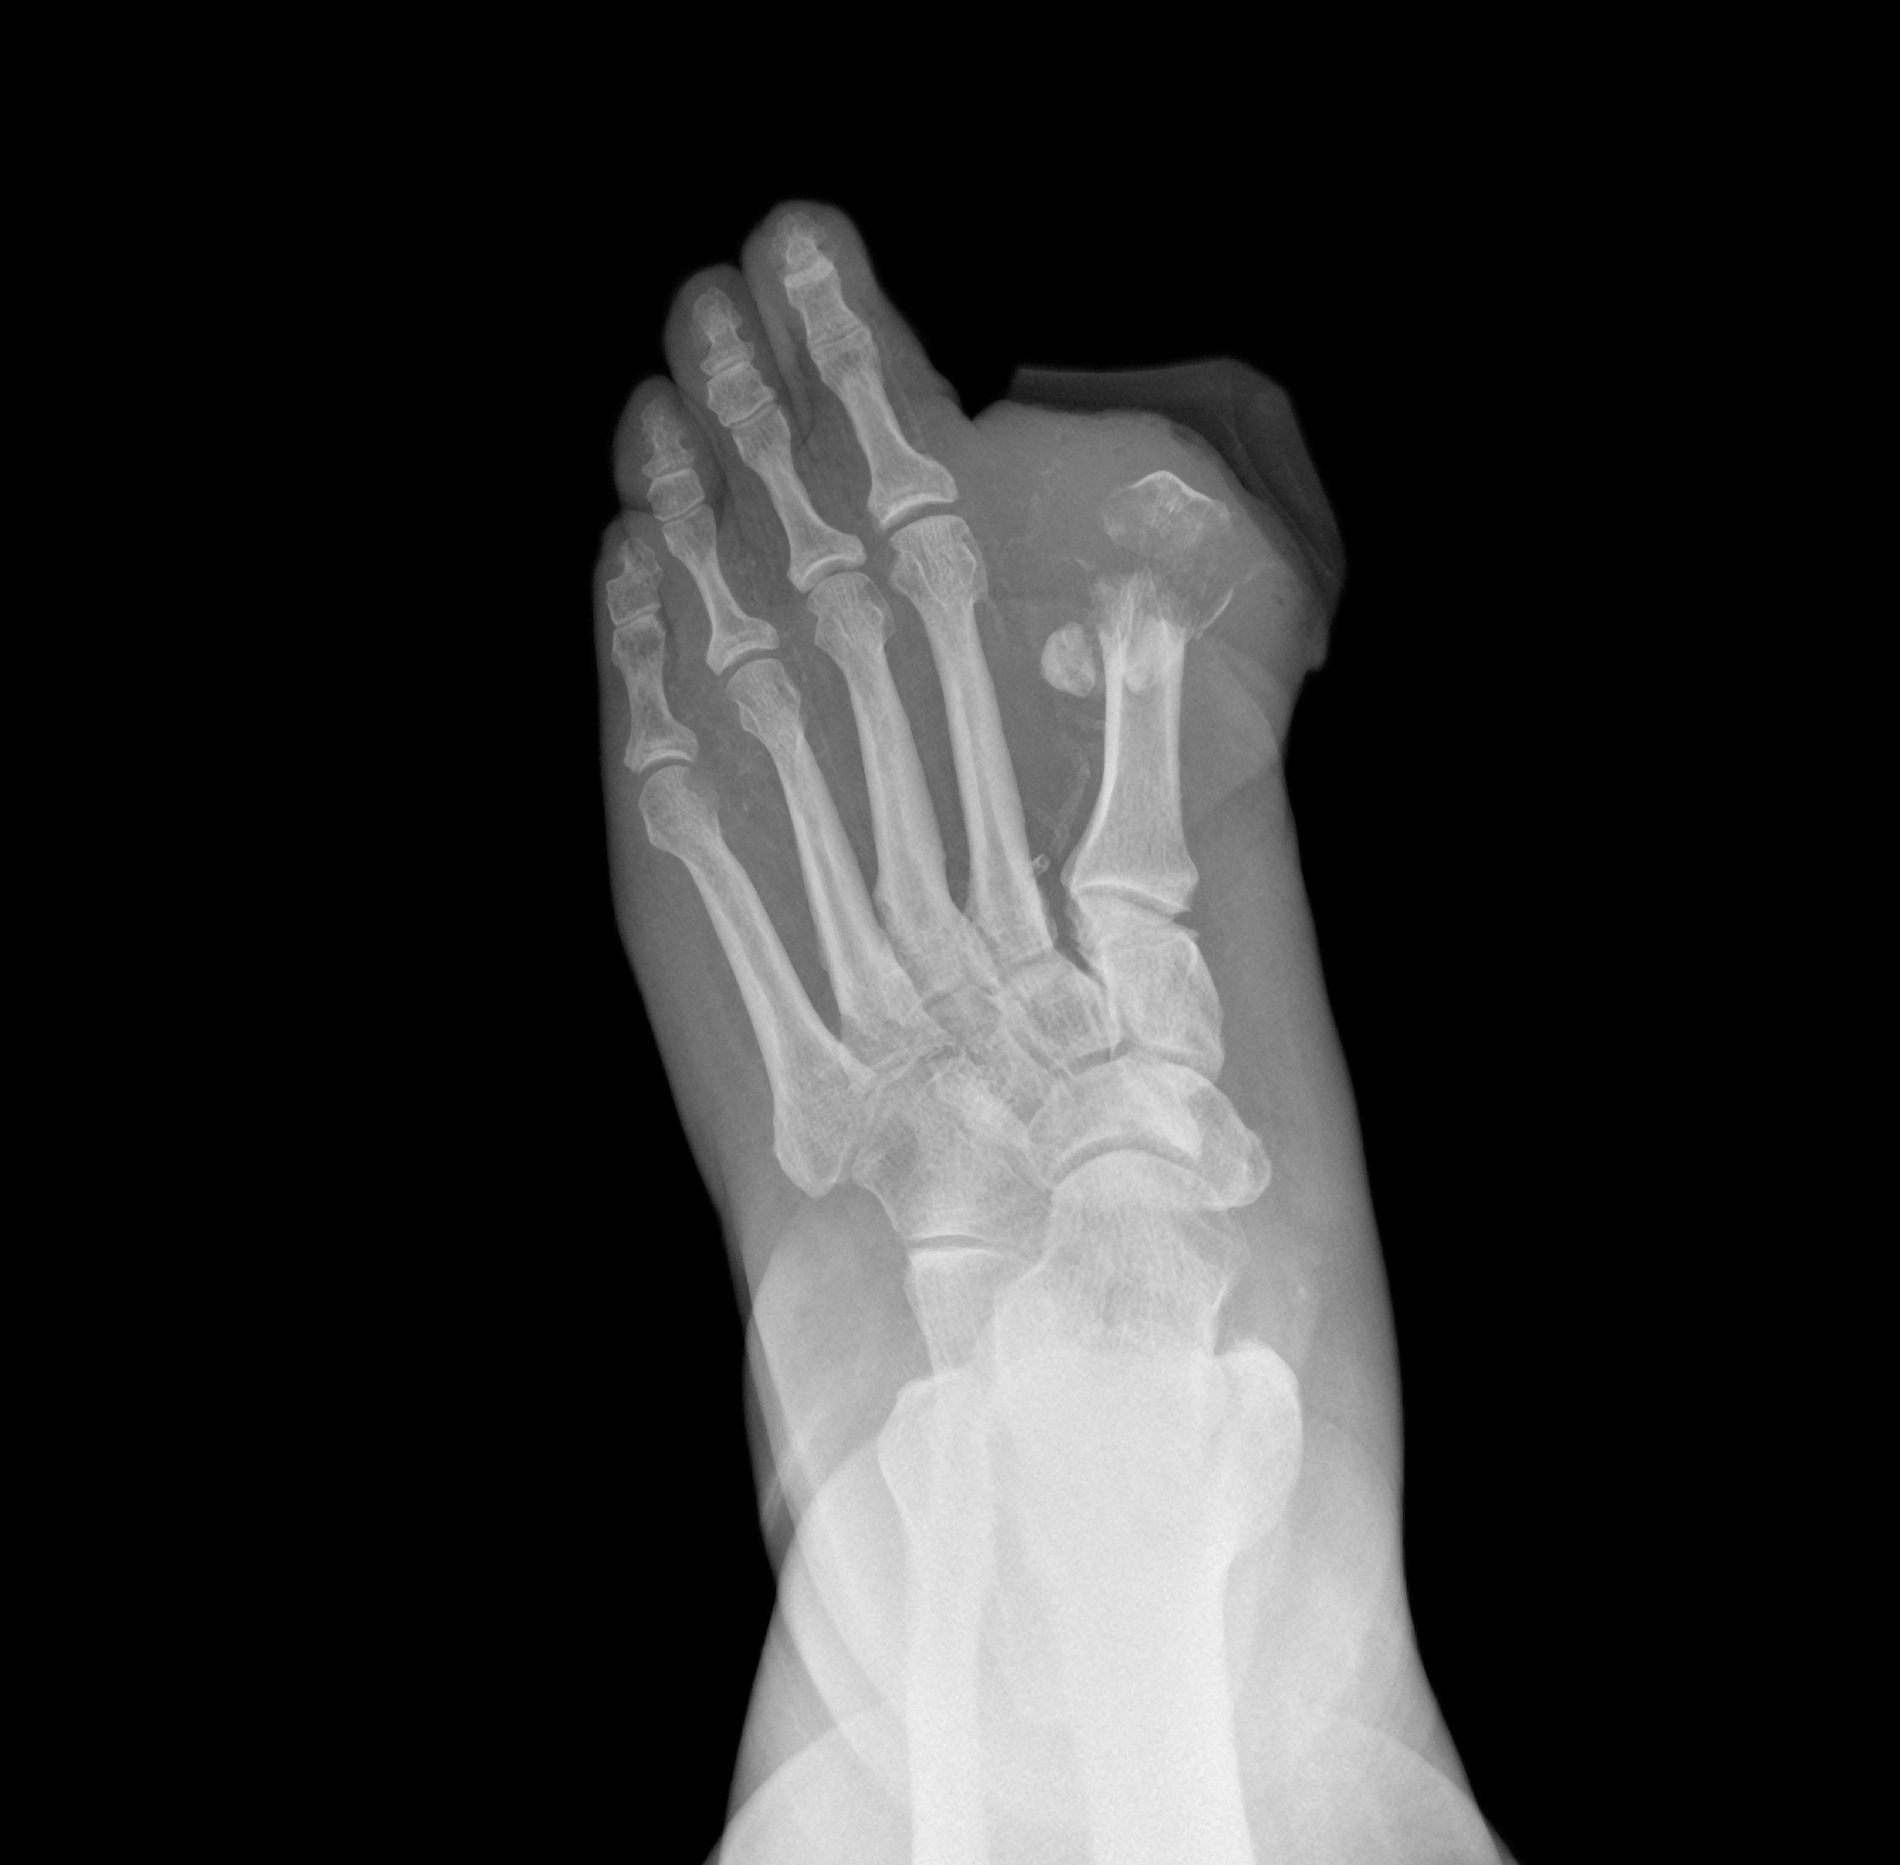

糖尿病足是指糖尿病患者由于长期高血糖导致的足部并发症。糖尿病足的主要原因是神经病变和血管病变,这使得患者对足部的疼痛和损伤感觉减退,同时也影响了足部的血液循环,容易引发感染和溃疡。